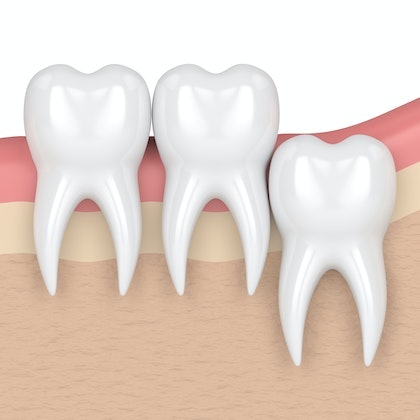

Take a Look

AT HOW WISDOM TEETH CAN CAUSE OVERCROWDING

In many cases, the small size of the jaw can become an issue when the wisdom teeth begin to come in. Even if the wisdom teeth erupt properly, they can cause your other teeth to shift. This can lead to misaligned teeth, which can also cause pain in the temporomandibular joints (TMJs). Extraction can prevent these issues.